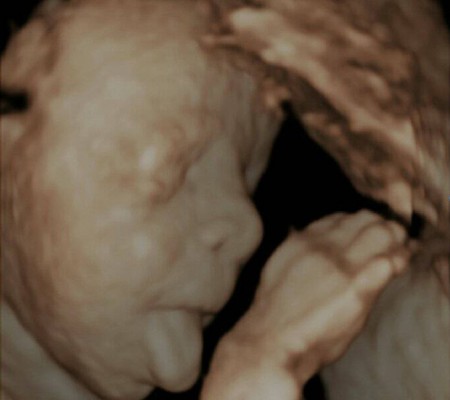

3D i 4D tehnologija omogućava da vidimo površinu bebe na lepši način i pokrete ploda u realnom vremenu.

Takođe nam omogućava da bolje vidimo fetalne mane na licu, šakama i stopalima.

Kao i 2D, 3D i 4D koriste ultrazvučni talas da se kreira slika bebe u materici. 3D je kreirana slika u prostoru dok 4D prikazuje pokret unutar materice pa možemo videti kako se beba smeje, mršti ili zeva.

Za prikaz ovih preseka potrebni su odgovarajući uslovi kao što su položaj ploda (lice ka nama), normalna količina plodove vode, poželjno je da ruke, noge i pupčanik ne budu ispred bebinog lica. U neodgovarajućim uslovima ovaj snimak nije moguće napraviti.

Da bi se dobile dobre slike poželjno je da se pregled radi između 24 i 32 nedelje trudnoće.